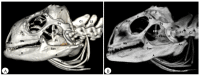

Anatomical Description of Loggerhead Turtle (Caretta caretta) and Green Iguana (Iguana iguana) Skull by Three-Dimensional Computed Tomography Reconstruction and Maximum Intensity Projection Images

The growing interest in reptiles has posed a challenge to veterinary clinicians due to the lack of a standardized system to perform anatomical studies similar to those used for dogs and cats. In this paper, we have attempted to describe, employing computed tomography and subsequent three-dimensional reconstructions, the normal anatomical features that comprise the skulls of two species of reptiles: the loggerhead turtle (Caretta caretta) and the green iguana (Iguana iguana). Computed tomography (CT) and subsequent image processing allowed the identification of the bony structures that comprise the head of these species. As a result, and based on previous articles, we propose the most significant anatomical differences and similarities between these species.